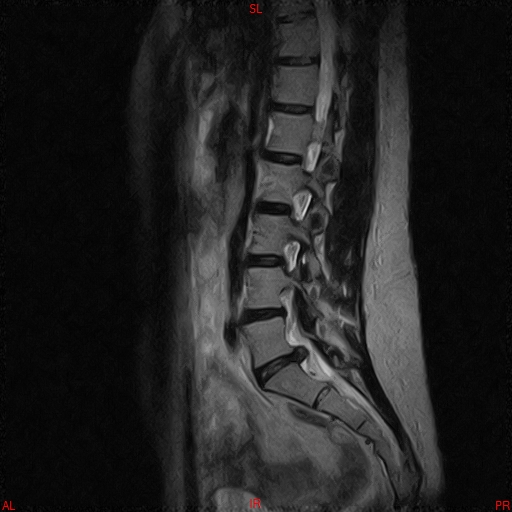

• RESONANCIA PATOLÓGICA DE C.LUMBAR - HERNIA DE DISCO L5-S1 -  SAG T2